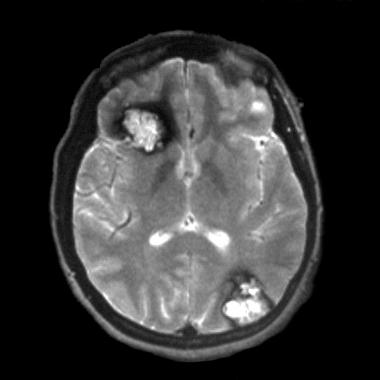

脑海绵状血管瘤磁共振诊断:附真实影像资料分析

脑海绵状血管瘤 是一组颅内血管畸形,是血管床发育畸形。这些先天性的、异常的血管连接往往随着时间的推移而扩大。病变可发生在家族基础上。患者可无症状,但常伴有头痛、癫痫...